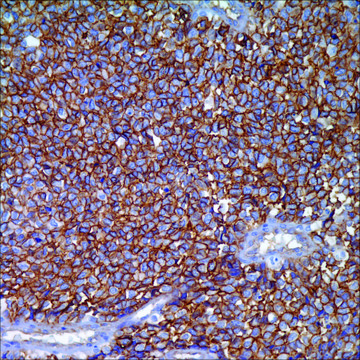

Ewing’s sarcoma

cytoplasmic, membranous

CD99, as detected with a variety of antibodies, is expressed by virtually almost all Ewings sarcoma and primitive peripheral neuroectodermal tumors (ES/PNET) and demonstrates strong and diffuse membranous staining. Other tumors that may show CD99 expression include neuroendocrine carcinomas, mesenchymal chondrosarcomas, solitary fibrous tumors, synovial sarcomas, vascular tumors, small round blue cell group of pediatric neoplasms, lymphoblastic lymphoma, acute myeloid leukemia, and myeloid sarcoma. However, strong and diffuse membranous reactivity for CD99 favors ES/PNET over the other diagnostic considerations. The other CD99+ tumors usually show cytoplasmic and more heterogeneous staining. Therefore, when making a final diagnostic interpretation, CD99 must be considered in a panel with other antibodies.